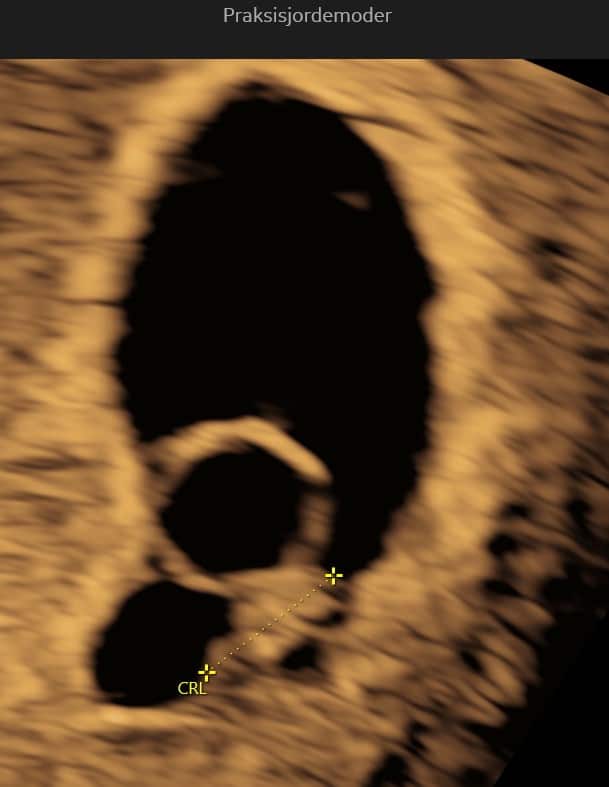

(6+0 til 6+6)

Embryoet bliver i denne uge omkring 1 cm langt. Arm- og benknopper bliver tydeligere, og vigtige organer som lever og mave begynder at dannes. Navlestrengen fungerer nu og transporterer næring og affaldsstoffer mellem dig og barnet.

I slutningen af uge 7 er din lille baby omkring 1,1 cm langt, omtrent på størrelse med et blåbær. Der sker mange vigtige udviklinger denne uge: